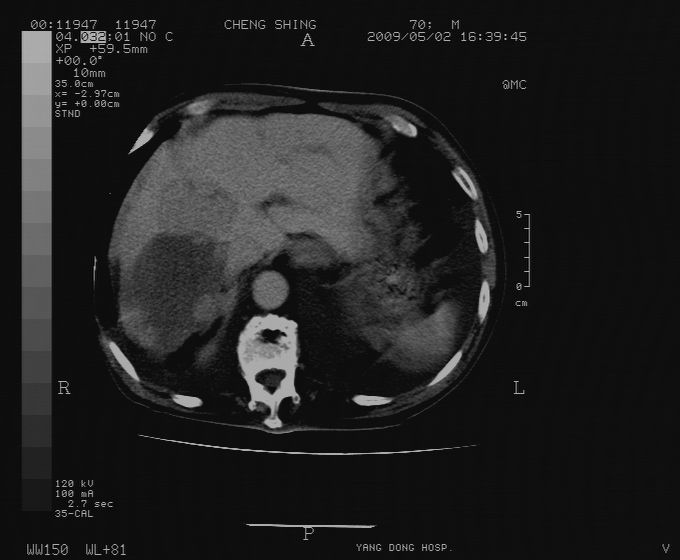

标题: CT19743:男70岁,肺部疾病入院,B超发现肝右叶占位,CT [打印本页]

标题: CT19743:男70岁,肺部疾病入院,B超发现肝右叶占位,CT

肝表面塌陷,病灶周围有子灶,前面较大子灶强化符合肝癌表现,考虑肝癌肝转移可能性大.

1.考虑肝癌肝转移

2.两侧胸水,左下肺不张!

1)考虑肝癌并肝内转移。2)少量腹水。3)双侧胸腔积液。

1)考虑肝癌并肝内转移。2)少量腹水及双侧胸腔积液。3)椎体退变。